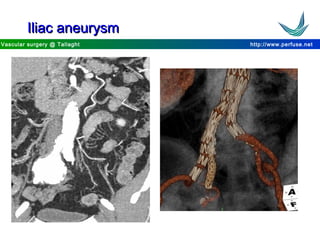

Iliac aneurysmIliac aneurysm

http://www.perfuse.netVascular surgery @ Tallaght